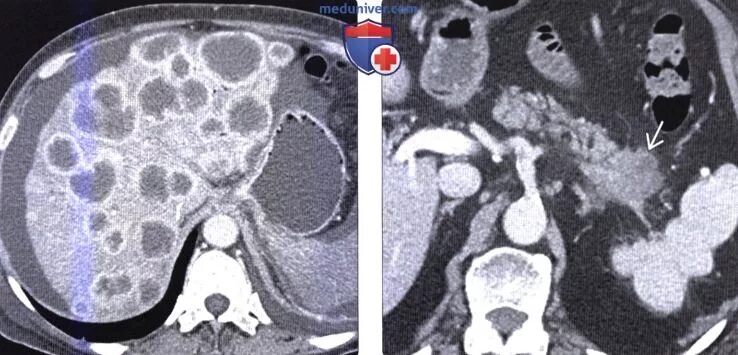

Метастазы в поджелудочную железу прогноз